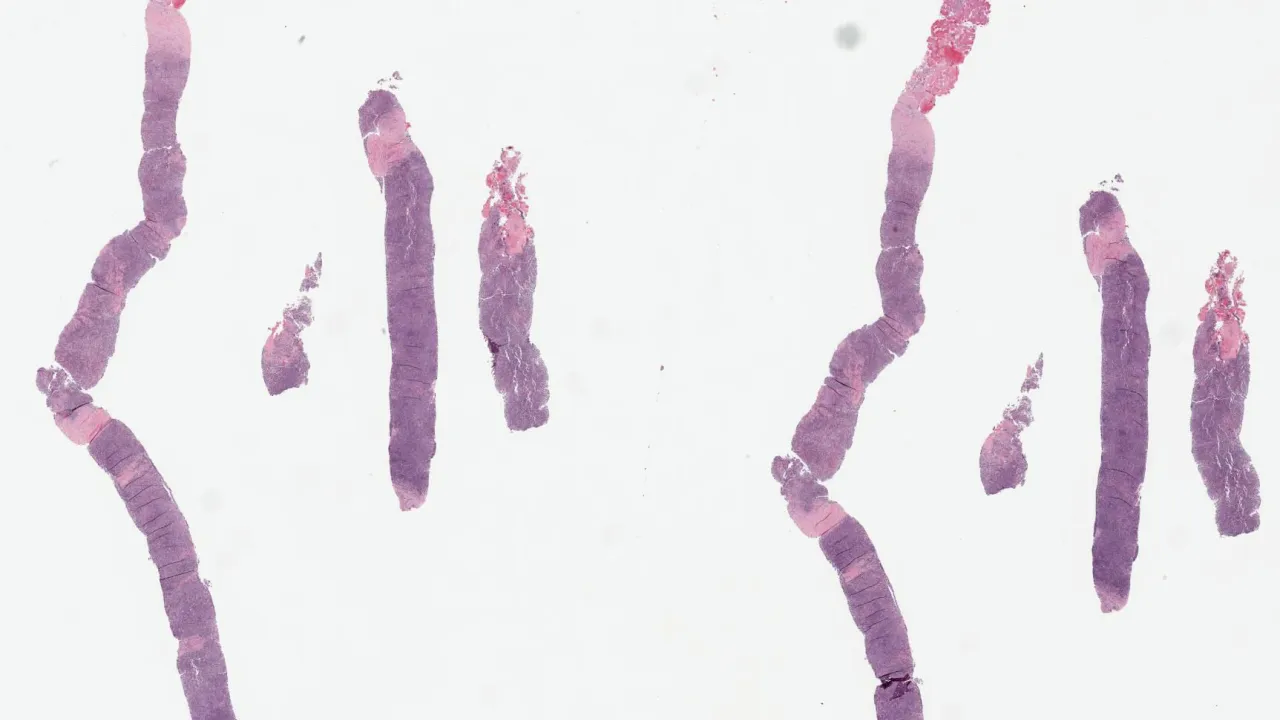

Lymph Nodes, Mantle cell lymphoma, H&E stain